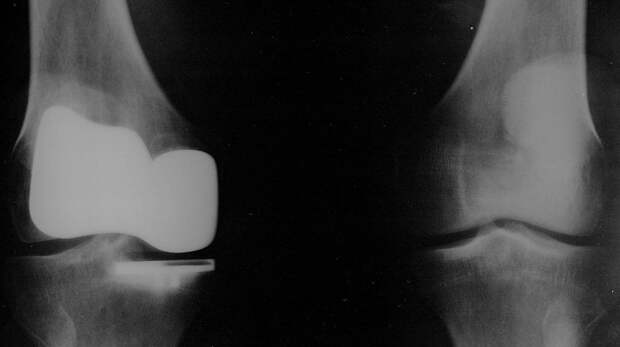

Около сорока эндопротезирований коленного сустава выполнили с весны этого года специалисты Центральной городской клинической больницы (ЦГКБ) Калининграда, сообщает 8 июня пресс-служба регионального правительства. В сообщении говорится, что калининградские врачи успешно освоили эндопротезирование коленного сустава.

Впервые такую операцию в городе сделали весной. До этого такие высокотехнологичные вмешательства выполняли в федеральных центрах. Последняя из числа проведенных операций по замене коленного сустава была сделана 66-летней жительнице Калининграда. Она прошла обследование в ЦГКБ, где врачи приняли решение об установке протеза. «Поставленный протез очень анатомичный и функциональный, он позволит пациентке быстро восстановиться и улучшит качество ее жизни», — рассказал об этом случае и. о. заведующего оперблоком ЦГКБ Максим Глинский. В свою очередь заведующий отделением травматологии и ортопедии ЦГКБ Алексей Федоров отметил, что освоение данной работы позволило резко сократить срок ожидания операции пациентом. Так, раньше очередь длилась несколько лет, а сейчас — три-четыре недели. При этом уже в течение двух-трех часов после операции больные становятся на ноги с помощью костылей.